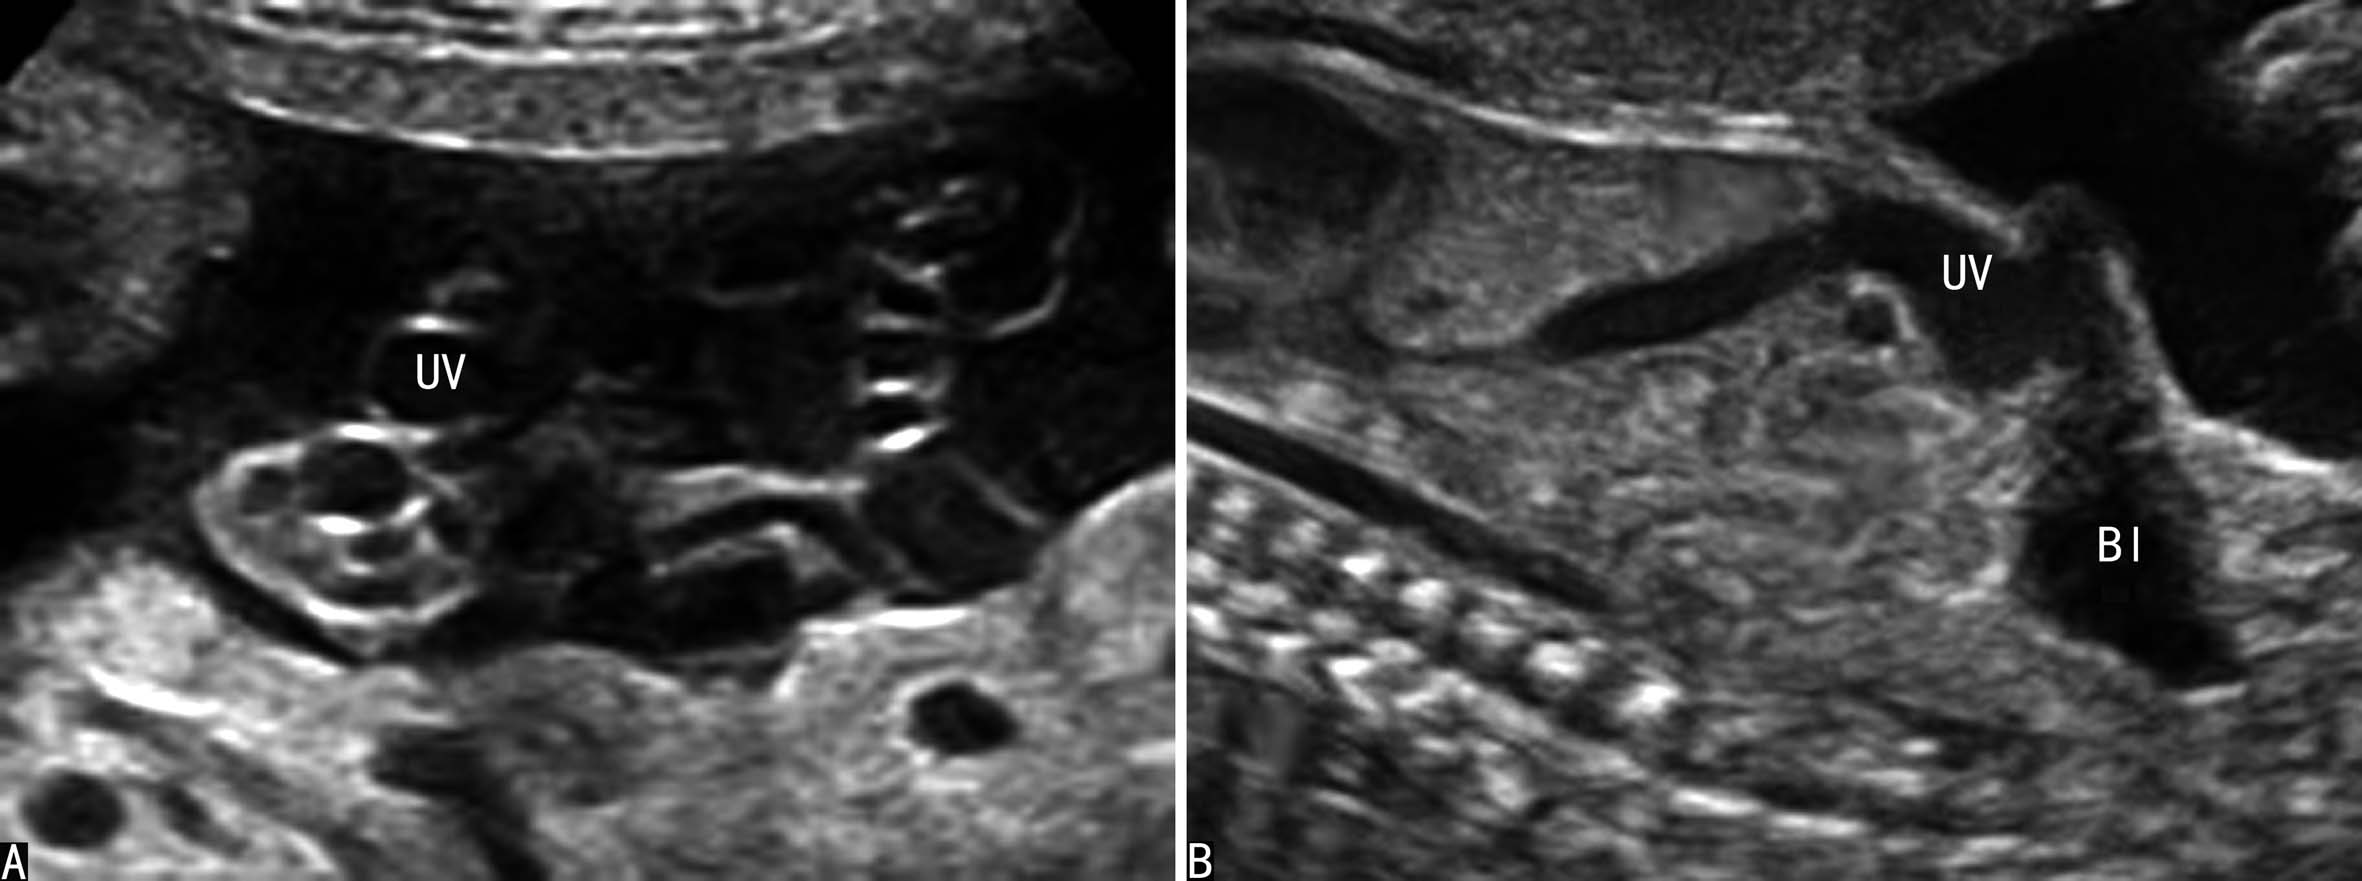

胎儿腹部横切面显示胃泡和脐静脉以后观察胆囊的位置可以确定脐静脉走行。正常脐静脉穿过脐轮后走行于胆囊的左侧,在胆囊与胃腔之间可以显示脐静脉的回声(图8A);如果在胆囊右侧显示脐静脉回声即可明确右脐静脉的诊断((图8B));肝内型持续性右脐静脉进入肝脏后PRUV需要转向左侧与静脉导管连接(图9)。连续追踪扫查如果显示脐静脉周围或一侧无肝脏实质,则提示为肝外型持续性右脐静脉。一般认为,后者常合并其他部位的发育异常,并可以合并染色体异常。

图8 正常脐静脉与持续性右脐静脉声像图比较